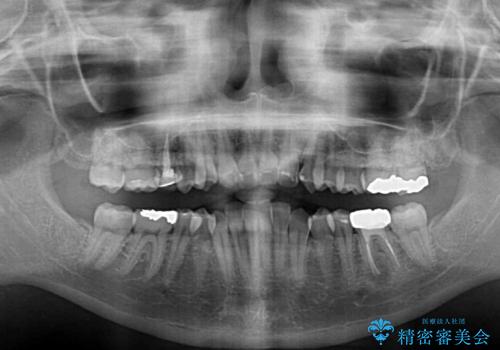

前歯のクロスバイト ギラギラのワイヤー装置で矯正治療

- 矯正装置

- メタルブラケット

- 前歯のクロスバイトを改善したいとのことで来院された患者様です。

マウスピース矯正では前歯の神経への負担が大きいことを懸念され、ワイヤー装置による矯正治療を行うこととしました。

クロスバイトが改善する際は、前歯しか接触しないため、痛みがあったり食事が取りにくかったりと、不便な時期がありますが、1年強の短期間で無事に治療を終えることができました。